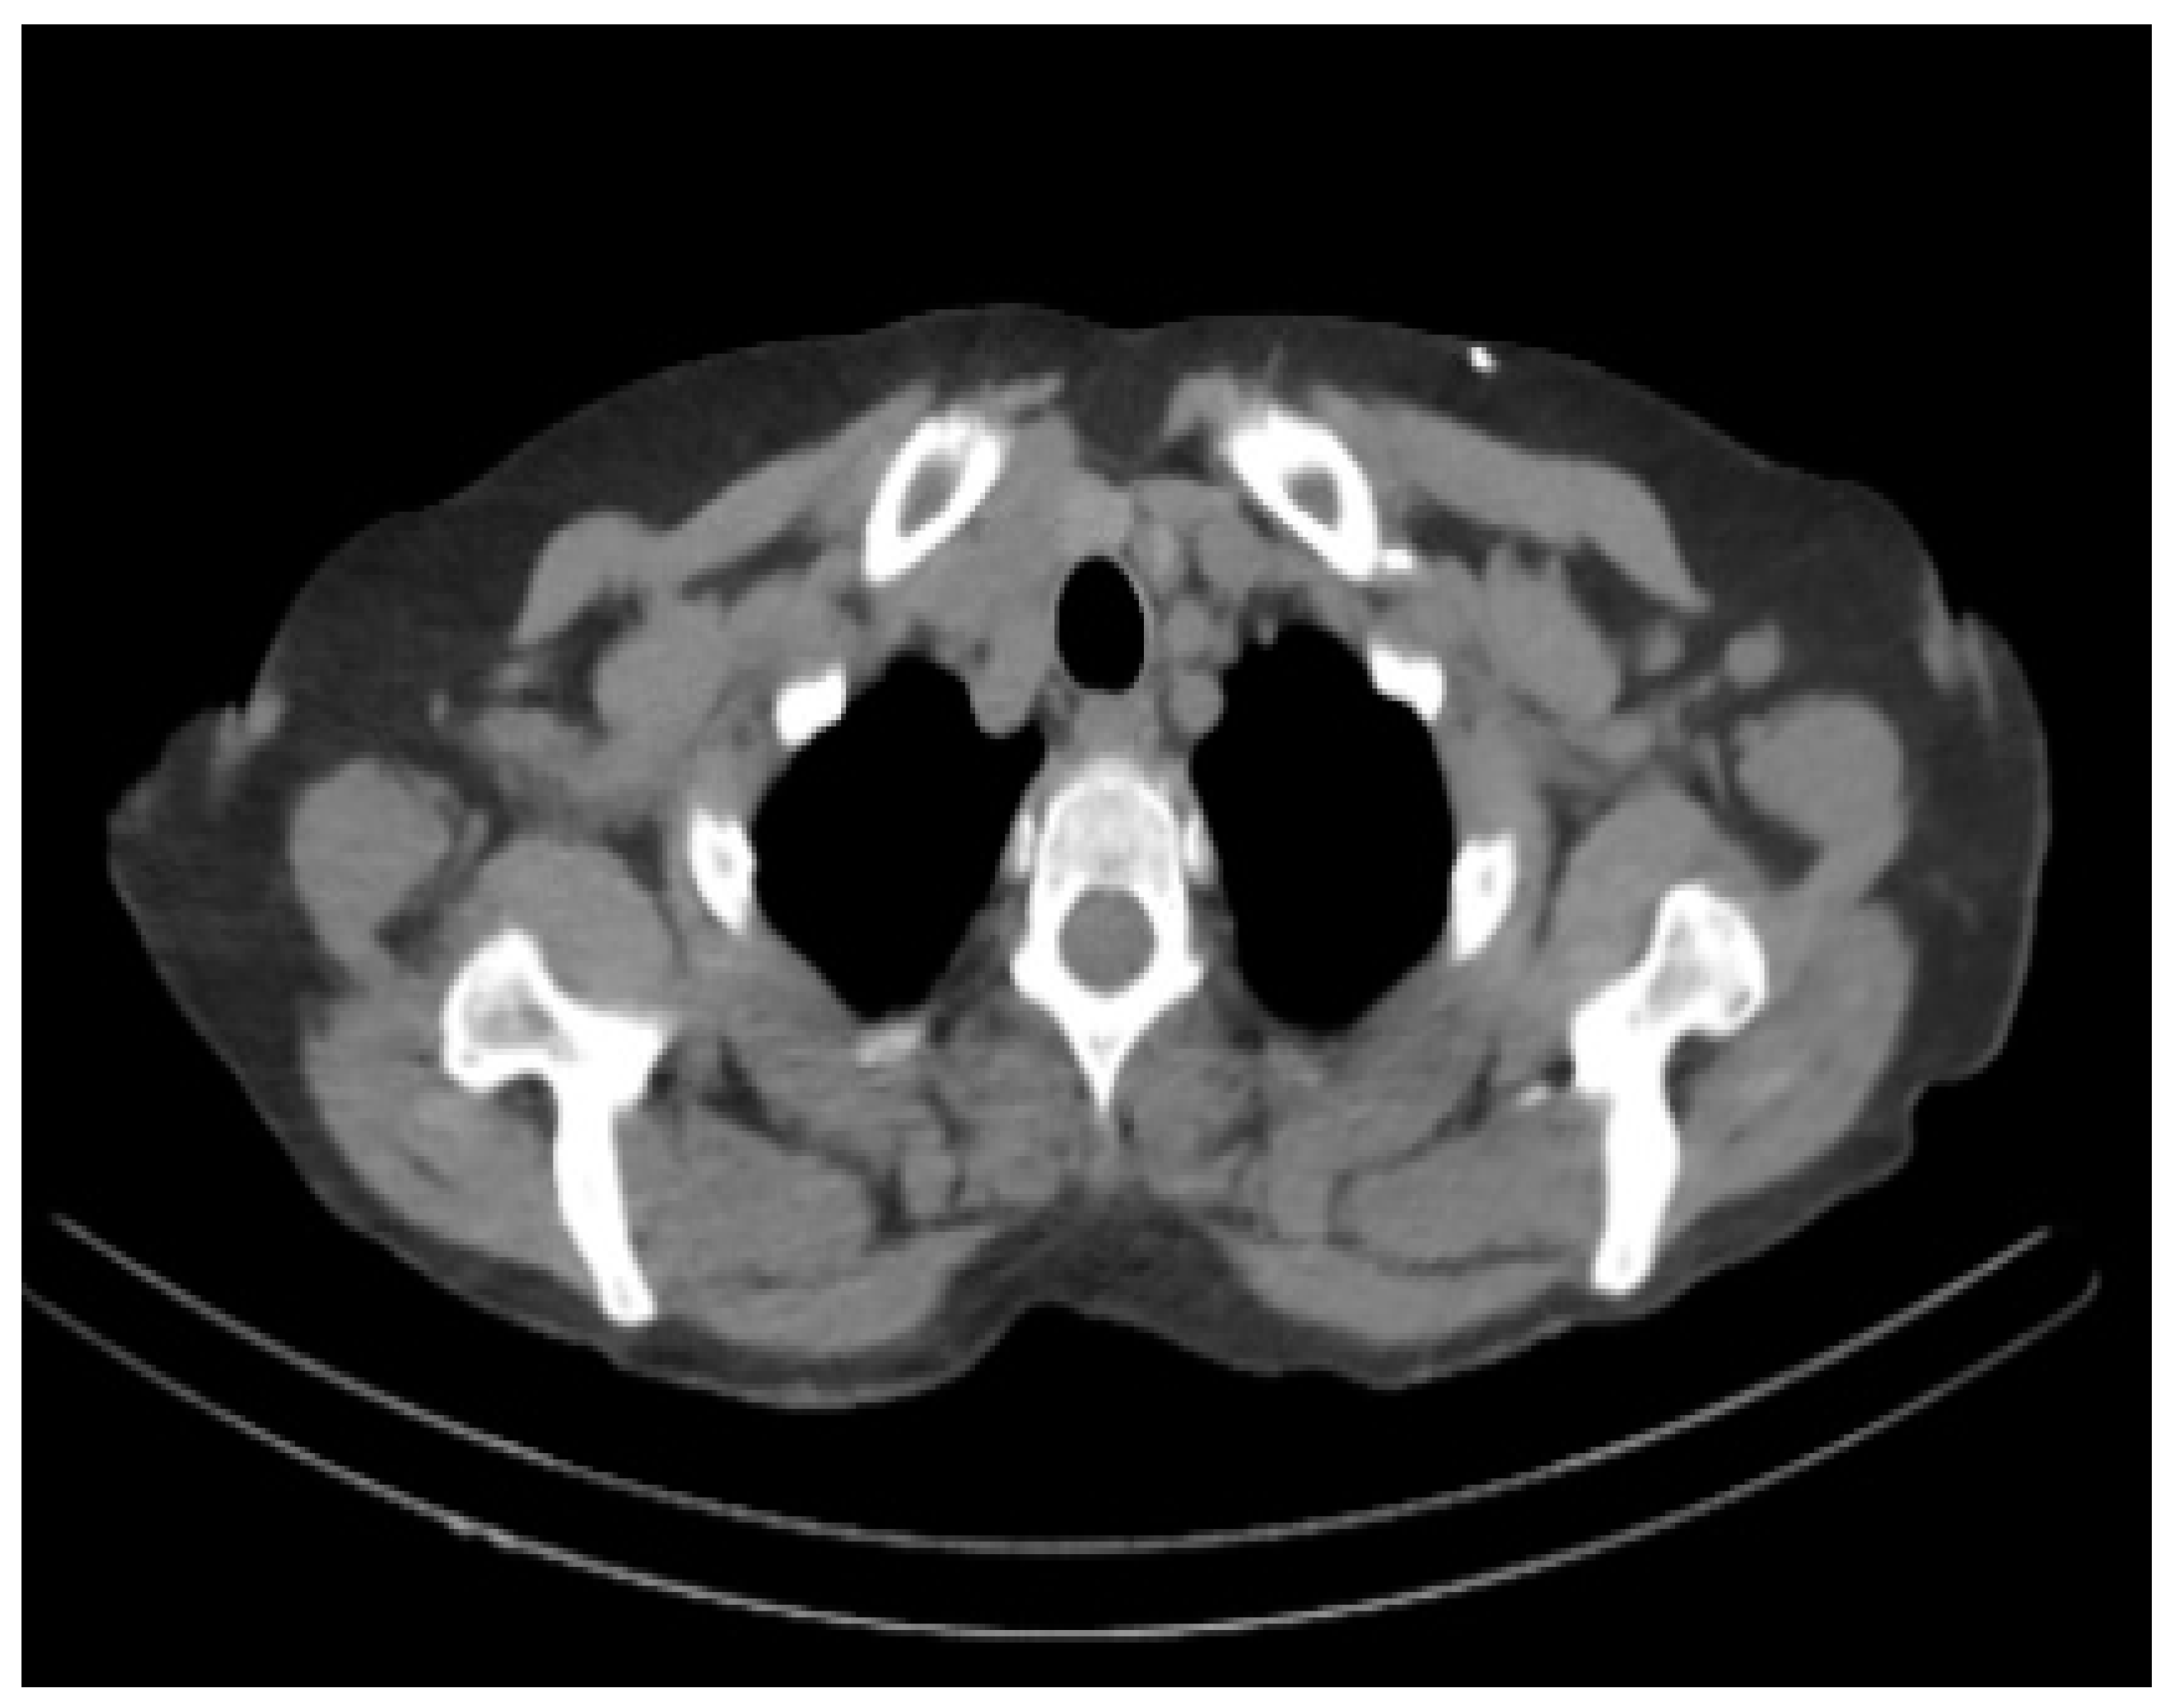

Figure 4.

Sample PET scan image showing an Alzheimer’s affected brain. Noted is the size of the enlarged ventricles.